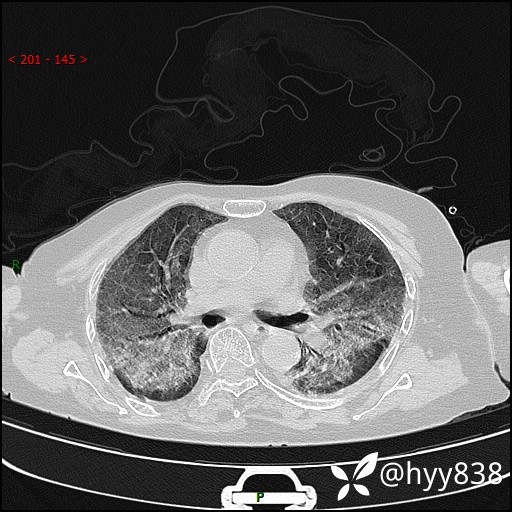

弥漫性肺部病变,辗转当地多家医院未能确诊,拟诊“重症肺炎”入我院--结果公布

患者年龄:69岁

简要病史: 患者20余天前无明显诱因出现发热,最高体温37.5℃,伴头晕,乏力,纳差等不适,无鼻塞,流涕,无咳嗽咳痰,无呼吸困难,无恶心呕吐、关节疼痛等不适,于当地市多家医院就诊,未明确病因,2023.6.23于当地第二人民医院就诊,完善胸部CT示病毒性肺炎,予以抗感染、清热解毒后症状较前稍好转,2天前患者无明显诱因出现活动后喘息加重,伴肌肉酸痛,口干,无明显咳嗽咳痰,今日体温38.1℃,为求进一步诊治来我院就诊,门诊以“ 重症肺炎 I型呼吸衰竭”收入院。 患者起病以来,精神、睡眠、饮食欠佳,大小便正常,体力下降,体重无明显改变。

辅助检查:CT

临床诊断:重症肺炎

胸部CT薄层扫描